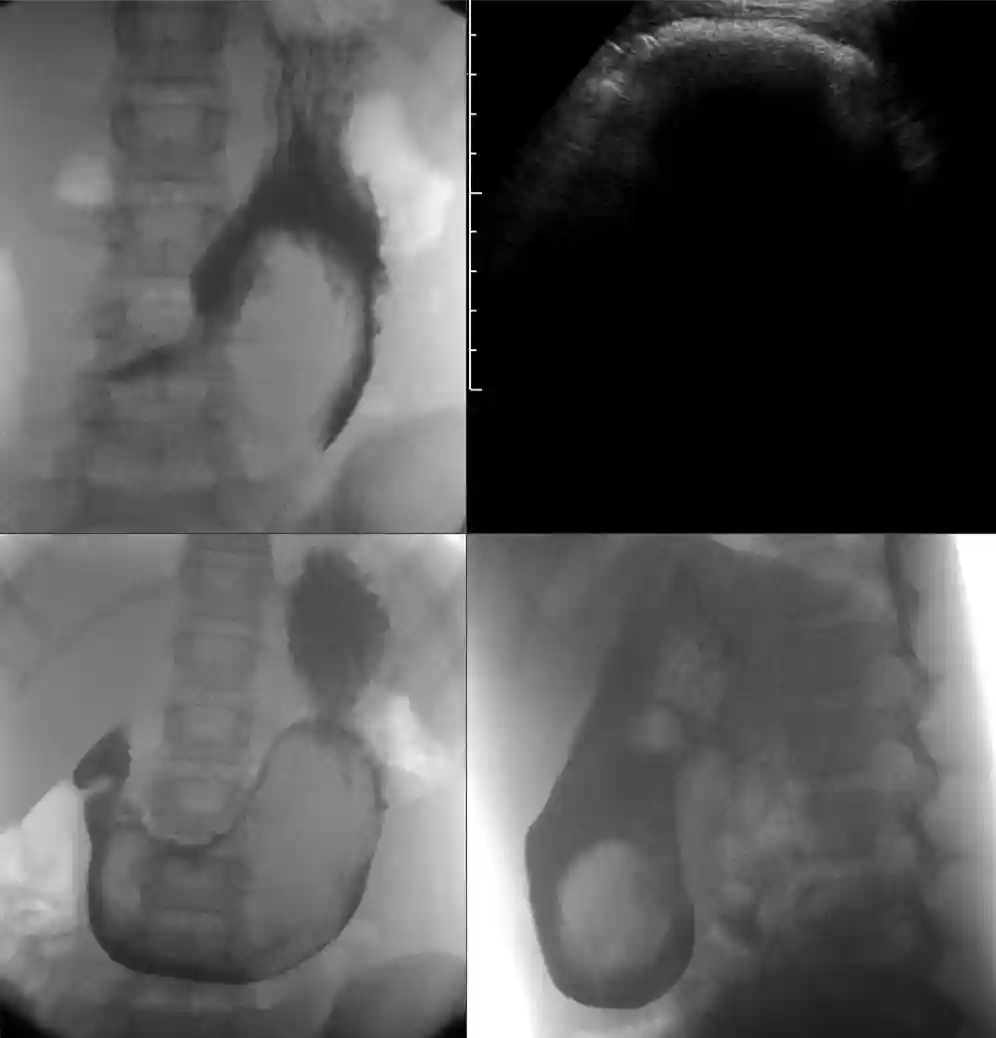

Un team di ricercatori presenta un caso insolito che coinvolge la scoperta del tricobezoario gastrico in una ragazza di 15 anni che aveva una malattia celiaca non diagnosticata. La condizione si è manifestata dopo che ha avvertito dolore addominale e pallore.

In un recente caso di studio, una ragazza di 15 anni ha presentato sintomi di tricobezoar, tra cui dolore addominale, vomito e perdita di peso inspiegabile. Dopo l'esame, i medici hanno scoperto una massa compatta nell'addome, insieme a segni di perdita di capelli sul cuoio capelluto. Ciò che ha reso unico questo caso è stata la successiva diagnosi di celiachia, patologia caratterizzata da una reazione avversa al glutine.

Il trattamento per il tricobezoario prevede in genere la rimozione chirurgica della massa, seguita da un supporto psicologico per prevenire le recidive. Nei casi associati alla celiachia, l’adozione di una dieta priva di glutine è essenziale per gestire i sintomi e favorire la guarigione. Questo approccio globale affronta sia gli aspetti fisici che quelli psicologici della condizione, offrendo ai pazienti la possibilità di migliorare la salute e il benessere.